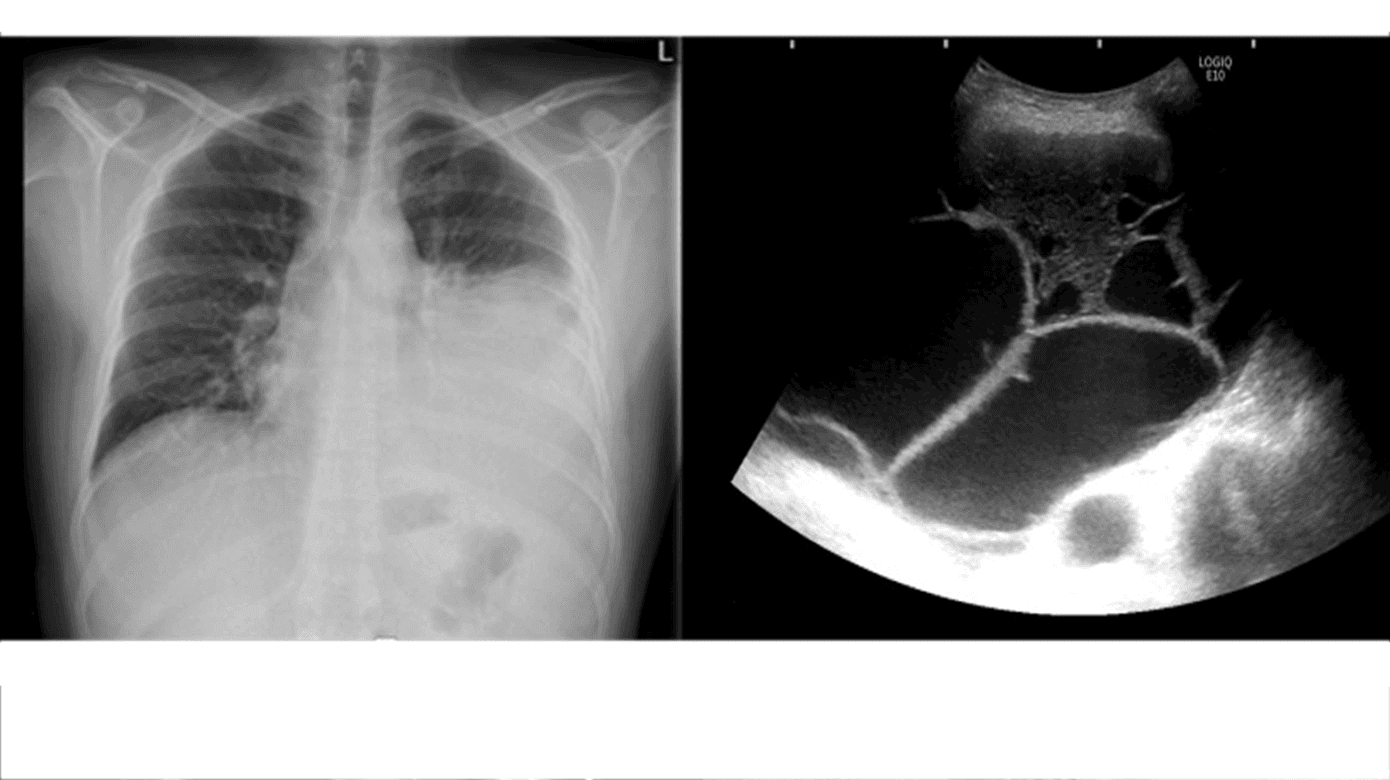

Thoraxrøntgenbillede med linseformet effusion kan give mistanke om pleurainfektion, men er inferiør i alle henseender sammenlignet med LUS og CT [3]. På CT af thorax kan fund som f.eks. konstrastopladning af pleura, pleurafortykkelse og lokulering være tegn på pleurainfektion, men er ikke diagnostiske [14]. LUS er røntgen af thorax overlegen til diagnostik af pleuraeffusion [1]. LUS er CT overlegen til at bedømme grad af lokulering og septadannelse [15] (Figur 2) og har derfor en central rolle i at identificere det optimale sted for pleurapunktur/drænplacering samt i kontrol af pleuraansamlinger både under indlæggelse og ved ambulant kontrol. CT af thorax med kontrast er LUS overlegen mht. at identificere lokaliserede væskelommer, som ikke er subpleuralt placeret (f.eks. langs mediastinum) og at afklare sygdom i lungeparenkymet såsom lungetumorer eller abscesser. Derfor kan CT af thorax med kontrast med fordel udføres initialt, hvorved skanningen kan fungere som en baseline til fremtidig sammenligning. Som minimum bør CT af thorax med kontrast udføres ved behandlingssvigt for at belyse mulige årsager og tilpasse behandlingsplanen [3].